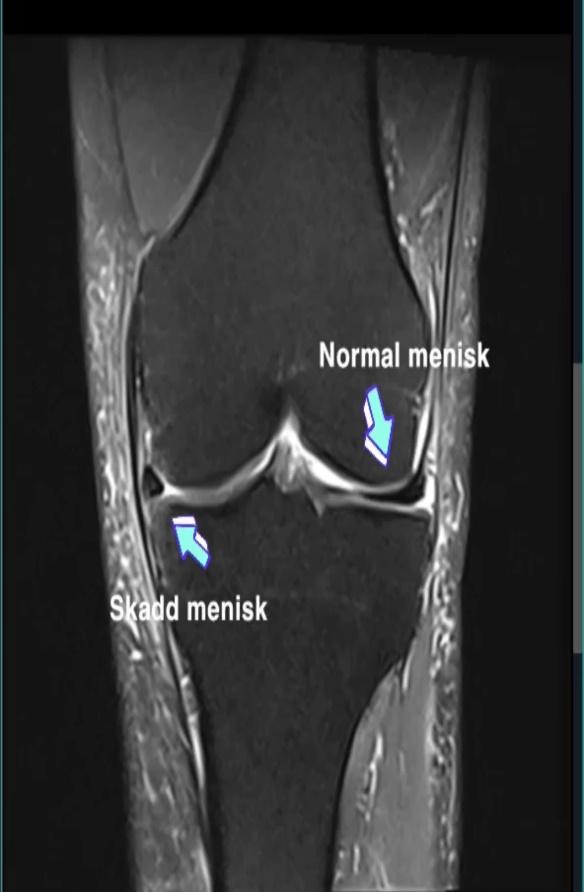

På grund af for meget løb på asfalt og minimal styrketræning blev belastningen for stor på knæ og meniskerne måtte derfor fjernes. I stedet fjernede de 2/3 af menisken i begge knæ.

Den 7. januar 2021 blev jeg opereret, og menisken i mit højre knæ blev fjernet på grund af belastningsskader og en rift i menisken. Operationen gik rigtig godt, og straks jeg vågnede fra bedøvelsen gik træningen i gang. Den første uge var det simple øvelser som siddende knæ-stræk og bøjninger var på menuen. Ugen efter operationen var det tid til min første tid hos en fysioterapeut, og det var her jeg fik en god introduktion til vigtigheden af styrketræning i kombination med løbetræning er. Både i forhold til skadesforebyggelse og forbedring af præstationen.

Efter to ugers blid løb begyndte jeg at føle den samme smerte i mit venstre knæ, og smerten var meget ens dem jeg havde haft i mit højre knæ tre måneder tidligere. Konklusionen var den samme, og det var en operation i den modsatte retning knæ.